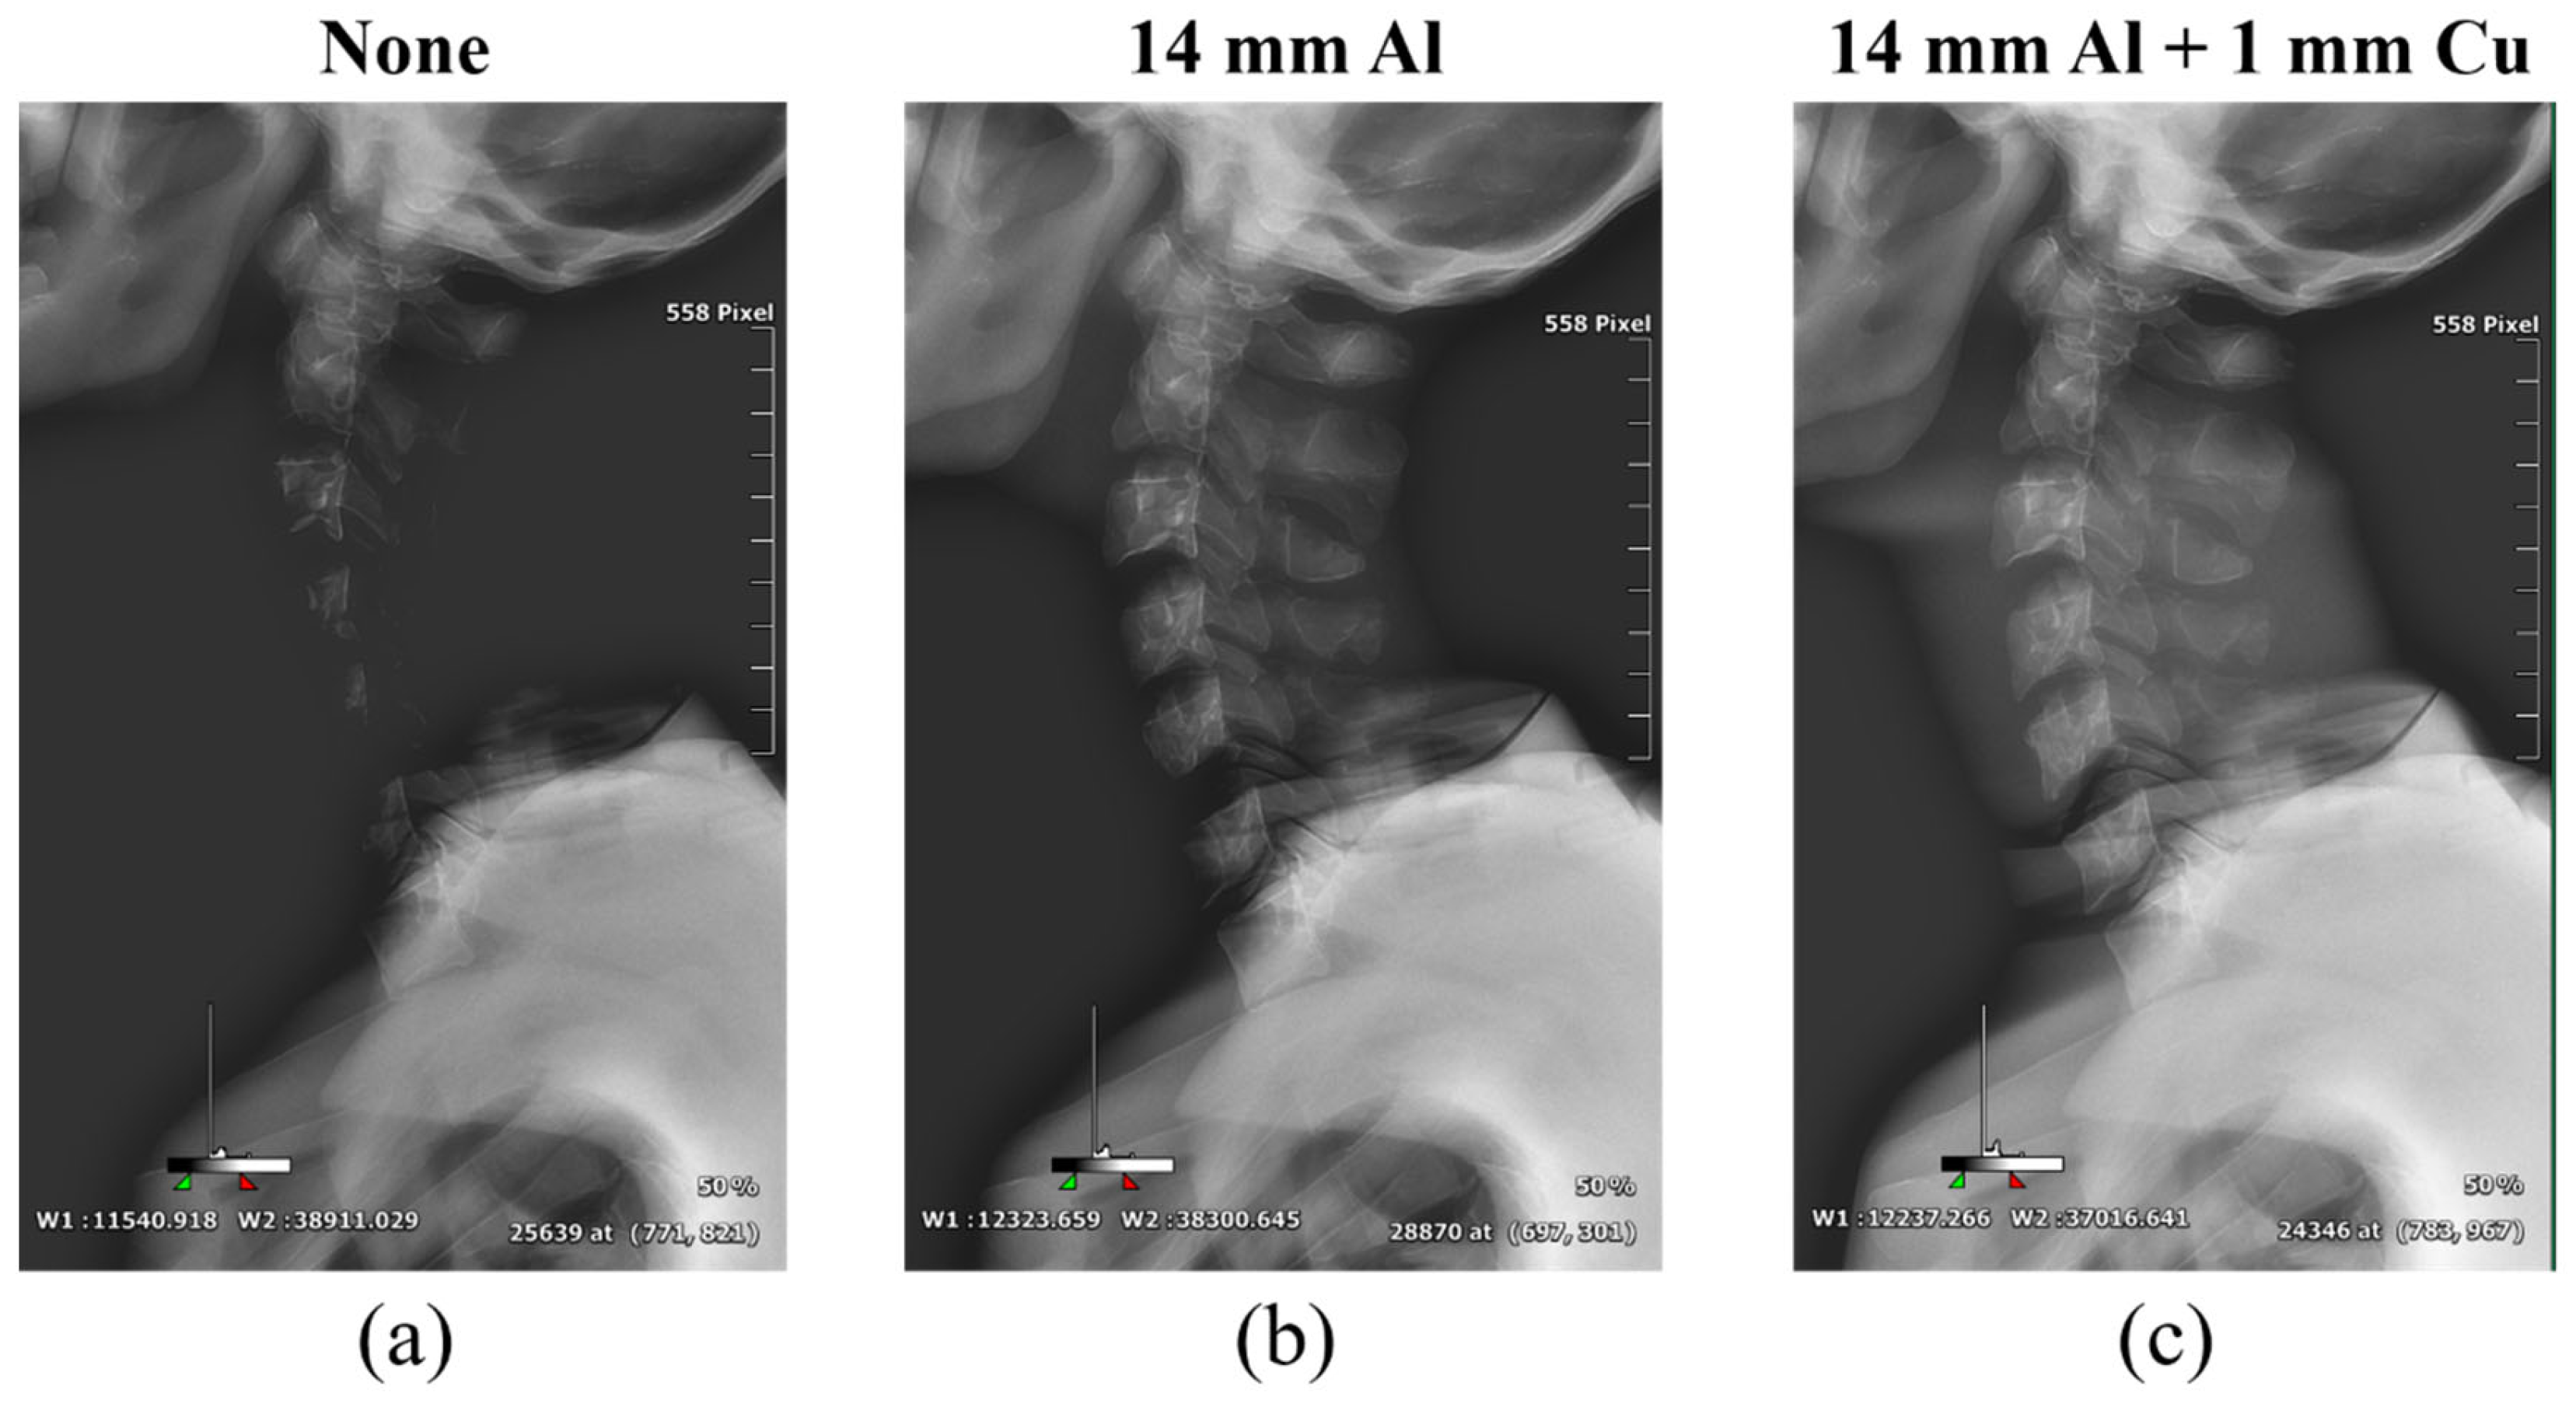

Figure 6, Figure 7 and Figure 8 show the acquired whole-spine AP, LAT, and long-leg AP X-ray images with and without additional filters, respectively. Visual evaluation of the obtained images confirmed that the image quality was improved when an additional filter based on Al and Cu materials manufactured with a 3D printer was used in thin areas such as the C-spine and ankle. In particular, the highest quality was observed in all the acquired X-ray images when a filter combining 14 mm thick Al + 1 mm thick Cu was used.

Figure 7.

Acquired whole-spine LAT X-ray images obtained without and with additional filters. (a) Whole-spine LAT image (a) without an additional filter, (b) with a 14 mm thick Al additional filter, and (c) with a 14 mm thick Al + 1 mm thick Cu composite additional filter.